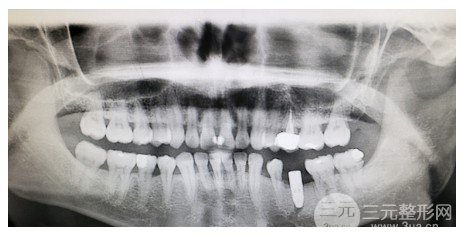

遲到拖延癥直到1月才去醫(yī)院復查拍片。片子顯示我骨密度太低,條件不好,暫時不能種植。醫(yī)生安慰了我很久,說我還年輕,不著急,就回家補鈣,然后找時間洗牙,等了三個月左右復查。

老師在我,之前看了這片子,因為半年后,他為我重拍了這部片子。得到結果后,他檢查了我,的口腔狀況,向我,以及手術的費用介紹了各種植入物的差異和價格。事實上,我是一個很容易被說服的人。不過老師都很優(yōu)質。都是華西的人才。在類似條件的情況下,并且因為我不是難種植的,它不是一種困難的疾病,所以我自然更喜歡一種方便的方式。然后去了華西醫(yī)生的門診。